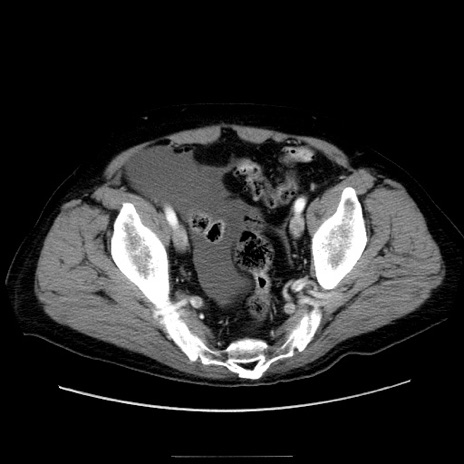

症例30(横断像)

【症例】80歳代男性

【主訴】臍周囲痛

【現病歴】約6時間前から臍下部痛が出現。次第に腹部膨隆・背部痛も生じてきたため来院。背部痛の場所は変化しない。

【身体所見】意識清明、BT 36.3℃、BP  131/87mmHg、P 87bpm、SpO2 100%(RA)、臍周囲自発痛・圧痛あり、反跳痛なし、自発痛部位に一致して板状硬あり、腹部膨隆、腸雑音減弱、CVA tenderness両側陰性。

【データ】WBC 19600、CRP 0.33